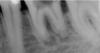

Ztn Опубликовано 18 июня, 2008 Поделиться Опубликовано 18 июня, 2008 Здравствуйте!Подскажите, можно ли как-нибудь спасти нижнюю шестёрку (на снимке)?Очень не хочется удалять. Ссылка на комментарий

АНРОША Опубликовано 19 июня, 2008 Поделиться Опубликовано 19 июня, 2008 А других способов кроме как через канал избавится от того что на корне зуба без его удаления зуба нельзя или в данном случае это невозможно?способы такие существуют, но в Вашем конткретном случае, думаю, что это невозможно... И вообще длина корней на этом зубе какая-то подозрительно укороченная... Наиболее оптимальным вариантом будет удаление с последующей имплантацией. Ссылка на комментарий